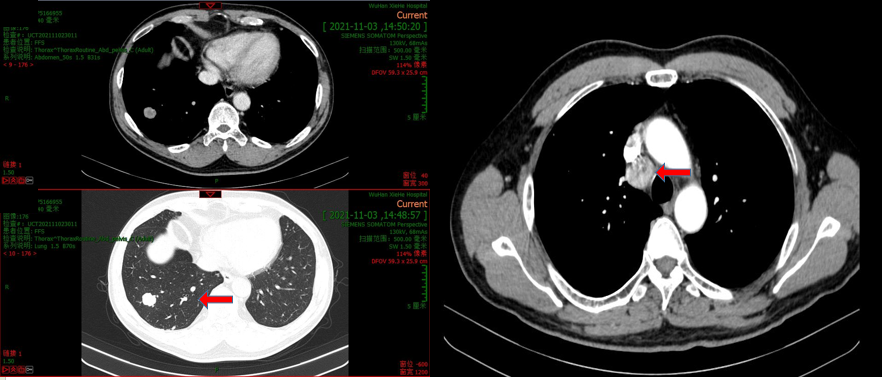

2021年10月31日我院行腹部+盆腔CT增强提示:左肾下极可见8.4*7.4*11.2cm肿块,部分与正常肾脏实质分界不清,其内可见坏死,增强扫描实性部分不均匀强化,疑累及包膜,肾静脉癌栓形成,位于同侧肾静脉内。所及肺内多发结节,较大者位于右肺下叶,约2cm,可见强化;符合肾癌(透明细胞癌可能性大,不除外合并异常分化),伴癌栓形成,疑肾周侵犯,部分性浸润型生长,可见双肺转移。

肺部CT平扫提示:

双肺散在多发实性结节影,大者位于右肺下叶,大小约2.0*1.7cm,转移瘤可能。纵隔及右肺门淋巴结增多、增大,大者约2.5*1.9cm,转移不除外。

影像学检查: